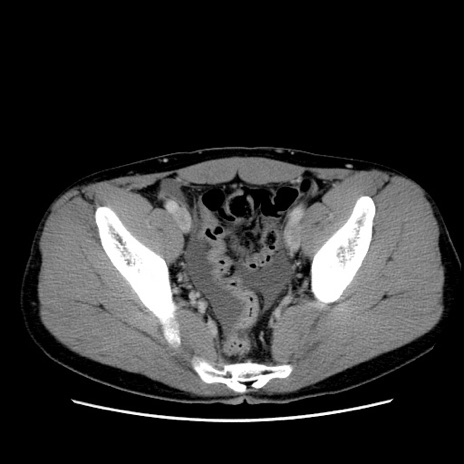

冠状断像

【症例】20歳代 男性

【主訴】心窩部痛

【現病歴】今朝より上腹部痛あり。一旦軽快していたが再度出現したため救急要請。昨日夕に白身の魚を含む刺身を食べた。

【身体所見】BP 136/89mmHg、HR 74/min、BT 37.0℃、腹部:膨満、軟、心窩部に圧痛あり。反跳痛なし、筋性防御なし、腸雑音やや亢進あり。

【データ】WBC 17700、CRP 0.48